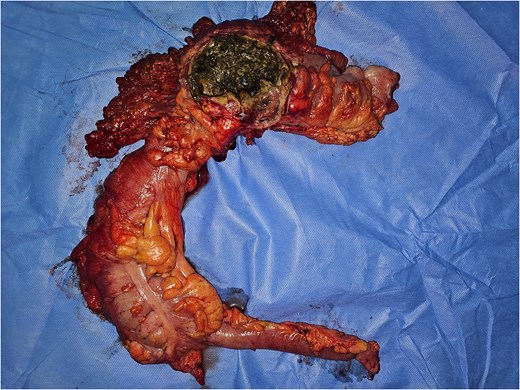

Emergency laparotomy revealed a large sealed perforation of the mid-transverse colon adherent to the first jejunal loop and omentum, purulent peritoneal effusion, and a fibrotic, inflamed duodeno-pancreatic block. The remainder of the gastrointestinal tract was unremarkable. A right extended hemicolectomy with double stoma, retroperitoneal lavage, and multiple drainages was performed (Figs 3–6).

Image of the surgical specimen of a right hemicolectomy showing the perforation.

The postoperative course was favorable under broad-spectrum antibiotics and intensive care support. Histology confirmed colonic wall necrosis and transmural inflammation without malignancy. The patient will be scheduled for a cholecystectomy (given the pancreatitis is gallstone-related) and a restoration of continuity in 3 months.